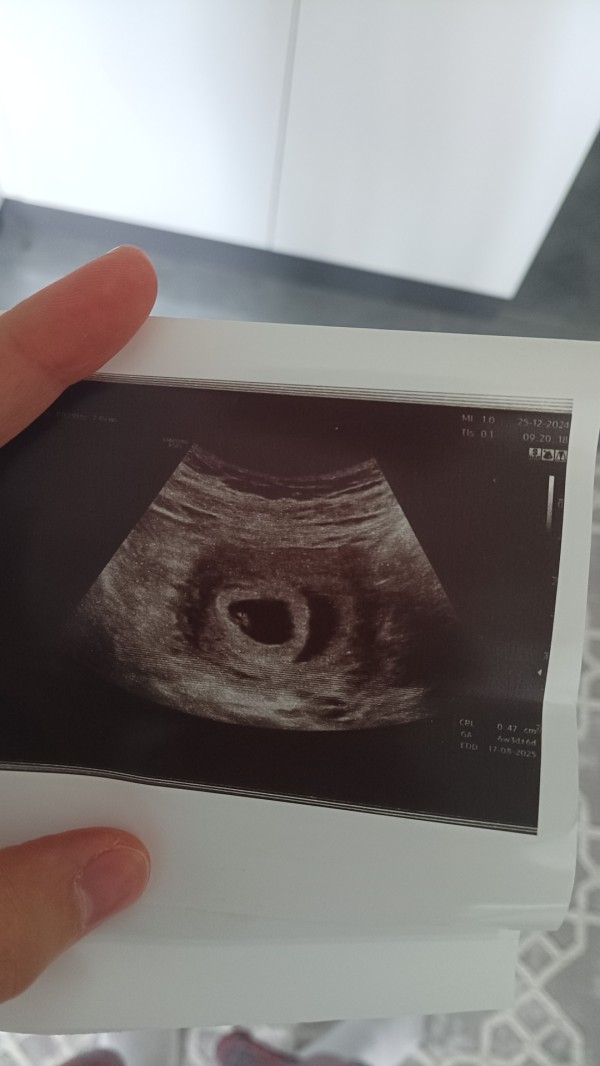

Merhaba kızlar öncelikle bu benim ablamın ultrasonu Ramiz teorisi diye birşey duydum bundan anlayan anneler ablamın bebeğinede bir tahminde bulunabilirmisiniz lütfen teşekkürler şimdiden

Bu benim kesemle aynı integramdan bı sayfaya baktırdım erkek dedi buda erkek gibi bebek sağda olunca erkek solda olunca kız oluyormuş

Benimki solda ama sağ sol meselesi duymuş bebeğin ilk ultrasonuna bakıyorlar kesenin içinde bebek sağda ise erkek solda ise kızmış benimki sağda idi bana erkek dedi

Benimde ilk haftalarda bu sekil ayni tarafta duruyordu kiz dedi doktor

Bu tur teoriler kisiden kisiye degisiyo bence tutanlarda oluyo illaki ama tersi olanda cok var en dogrusu doktorun dedgi oluyor 16. haftayi beklemek lazm tabi

ayni tarafta sağ tarafta değiller mi

Merhaba canm bu benim ablamın şuan 13 haftalık ana daha öğrenemediler öğrenince buraya yazarım